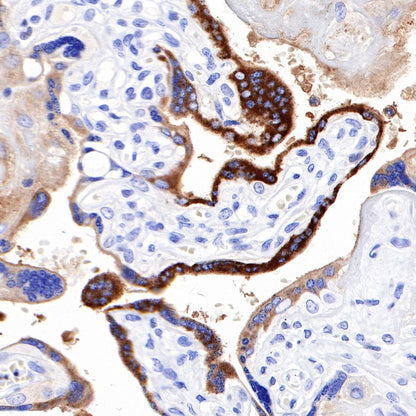

Negative control: IHC shows negative staining in paraffin-embedded human testis. Anti-PAPP-A antibody was used at 1/1000 dilution, followed by a HRP Polymer for Mouse & Rabbit IgG (ready to use). Counterstained with hematoxylin. Heat mediated antigen retrieval with Tris/EDTA buffer pH9.0 was performed before commencing with IHC staining protocol.